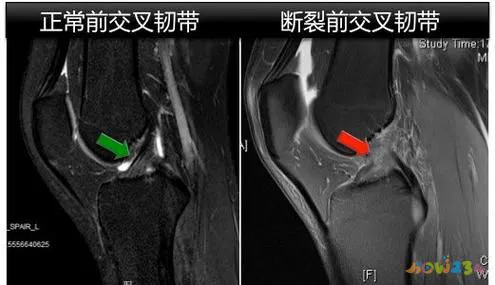

如果您患有 ACL 损伤或怀疑您患有 ACL 损伤,请立即停止锻炼并避免负重或移动膝盖。使用冰袋冷却受伤部位并抬高受伤的腿部以减少肿胀。尽快去看医生,医生将通过体格检查、特殊检查(如前抽屉检查)和影像学检查(如 MRI)来确认损伤程度。治疗基于损伤的严重程度、患者的运动需求和生活方式,通常分为保守治疗和手术治疗。